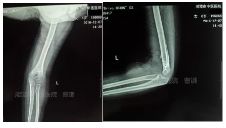

外院片如下:

杨氏四步复位法整复后拍片复查